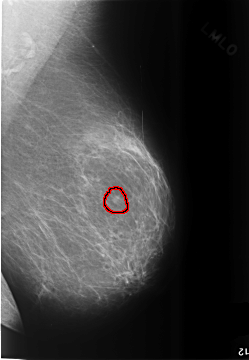

C_0496_1.LEFT_MLO

LEFT_MLO LINES 5752 PIXELS_PER_LINE 3976 BITS_PER_PIXEL 12 RESOLUTION 50 OVERLAY

FILE: C_0496_1.LEFT_MLO.OVERLAY

TOTAL_ABNORMALITIES 1

ABNORMALITY 1

LESION_TYPE CALCIFICATION TYPE AMORPHOUS DISTRIBUTION CLUSTERED

ASSESSMENT 4

SUBTLETY 3

PATHOLOGY MALIGNANT

TOTAL_OUTLINES 1

BOUNDARY